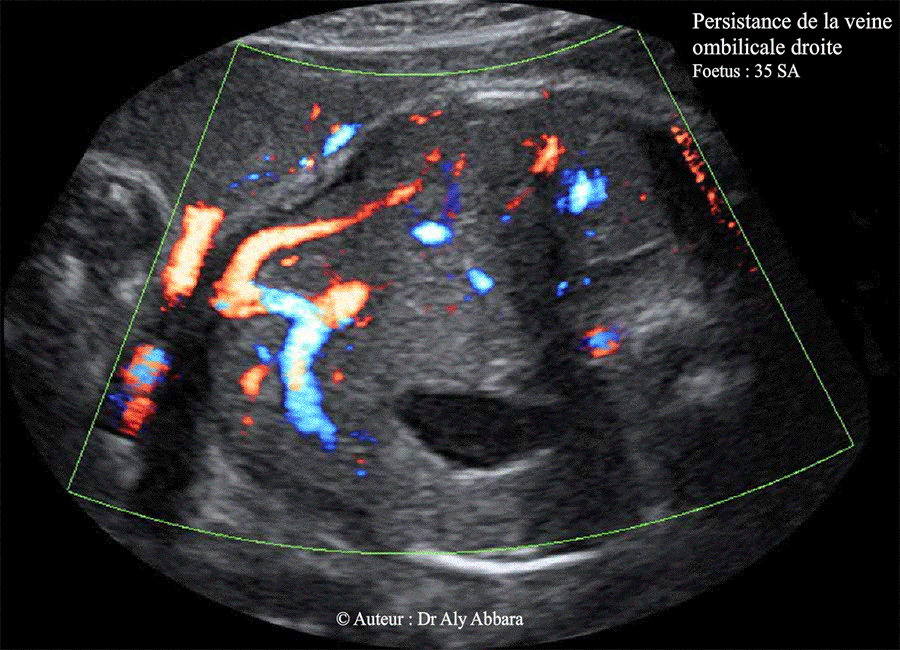

Veine ombilicale droite persistante - 35 SA - Images - Doppler

Images échographiques montrant une veine ombilicale à deux branches droites, la première est extra-hépatique et la deuxième est intrahépatique ; puis un trajet inhabituel de la branche gauche de de la veine ombilicale qui se dirige vers la région anatomique à gauche de l'estomac.

Le canal veineux naît de la veine ombilicale comme une branche intermédiaire qui n'atteint pas la veine cave inférieure sur aucune coupe réalisée lors de l'étude Doppler de cette anomalie.

(Variante de la veine ombilicale droite persistante ?).

Foetus de 35 SA ; aucune anomalie morphologique associée ; foetus eutrophe à la naissance.

b- Veine ombilicale à deux branches droites, extrahépatique et intrahépatique

(le cas présenté dans cette page)